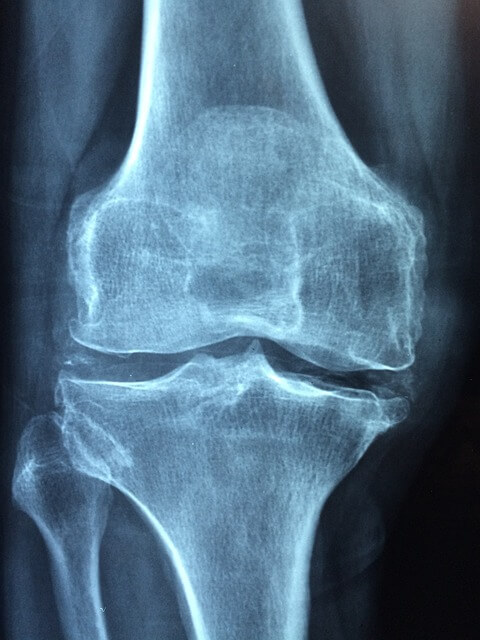

관절보궁은 관절 건강에 도움을 주는 다양한 효능을 지닌 제품입니다. 주요 성분인 글루코사민과 콘드로이틴은 관절 연골을 보호하고, 통증 완화에 효과적입니다. 또한, MSM(메틸설포닐메탄)은 염증을 줄이고 관절의 유연성을 증가시키는 데 도움을 줍니다. 이러한 성분들은 관절의 기능을 개선하고, 일상생활에서의 활동성을 높여주는 데 기여합니다. 특히, 노화로 인한 관절 문제나 운동 후의 피로 해소에도 효과적이며, 꾸준한 섭취를 통해 관절 건강을 유지할 수 있습니다.